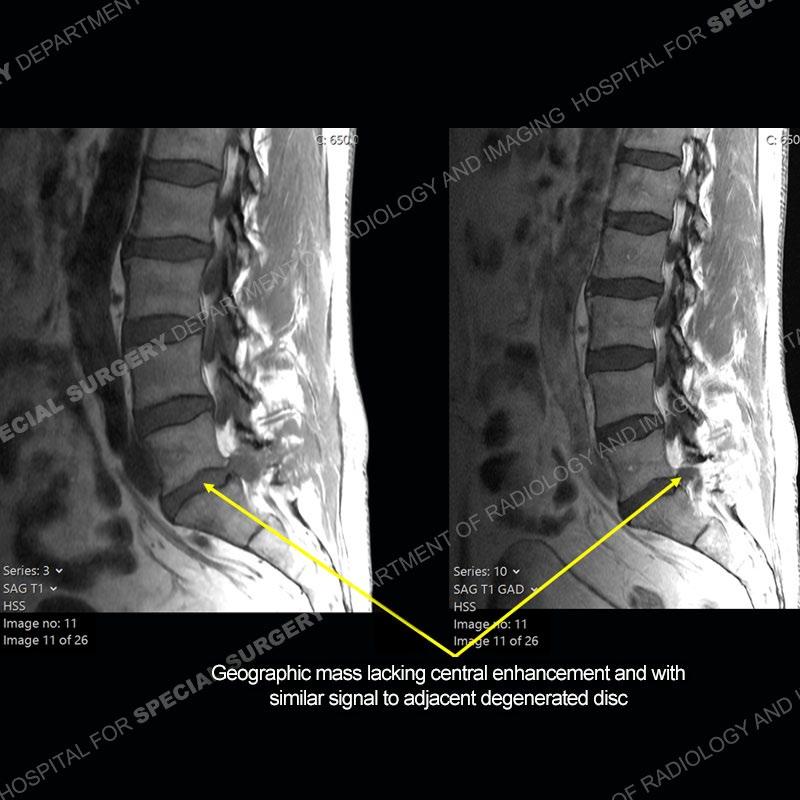

Post operative changes are seen on the left side at L5-S1 where there is near complete removal of the left sided L5 lamina, partial resection of the left L5-S1 facet joint, and resection of the left sided ligamentum flavum. In the anterolateral epidural space about the subarticular recess is a mass that demonstrates similar T1 and T2 signal characteristics to the adjacent degenerated disc. There is enhancement about the periphery of the mass, but the majority of this somewhat geographic or polyploid mass demonstrates no enhancement. The mass exerts prominent mass effect on the left S1 axillary sleeve/proximal nerve root. The left S1 nerve root shows enlargement and increased enhancement as compared to the contralateral right side.

Not as much of a diagnostic dilemma as some other cases but more so just a very nice example of what can be a difficult assessment at times. The evaluation of granulation tissue/scar/epidural fibrosis vs. disc herniation particularly in the earlier post operative period can be very difficult. Clues that can assist in identifying a disc herniation are a more geographic or polypoid nature to the mass, signal characteristics similar to the adjacent degenerated disc, mass effect upon the thecal sac/adjacent neural structures, and a typical enhancement pattern. As the disc material is avascular, as long as imaging is performed in a relatively rapid fashion after contrast administration (within 20-30 minutes), the granulation tissue around the disc will enhance but the disc material itself will not. If there is a marked delay between contrast administration and imaging, there may be diffusion of contrast into the disc making the assessment very difficult. The marked utility of contrast to help delineate disc vs. scar has led to our institution employing contrast fairly uniformly within the first two years following surgery.